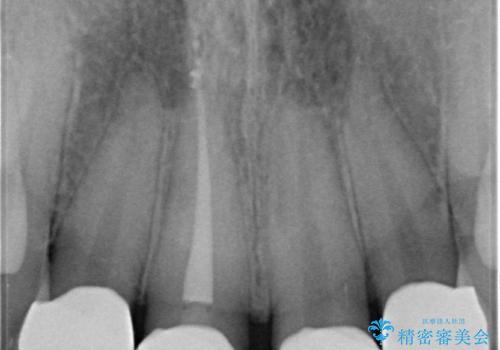

- 前歯を綺麗にしたいとの事で来院。

まずは仮歯を発注して仮歯にして最終的な被せ物の形を整えてジルコニアクラウンstで処置を行いました。